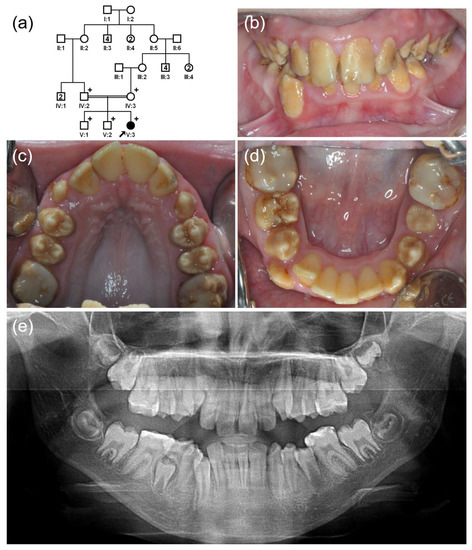

3.3. Family 3